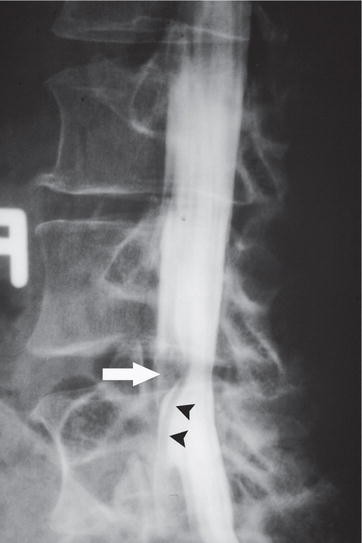

After the discovery of x rays by roentgen 1895 radiology developed as a medical specialty in 1897 the belgian government suggested that all hospitals should be equipped with x ray apparatuses evidencing the importance of the method for radiodiagnosis 23a radiology service can comprise methods relying both on ionizing and non ionizing radiations covering conventional. One milliroentgen abbreviated mr is one thousandth of a roentgen. Radiology service design guide april 2008. The naked facet sign.